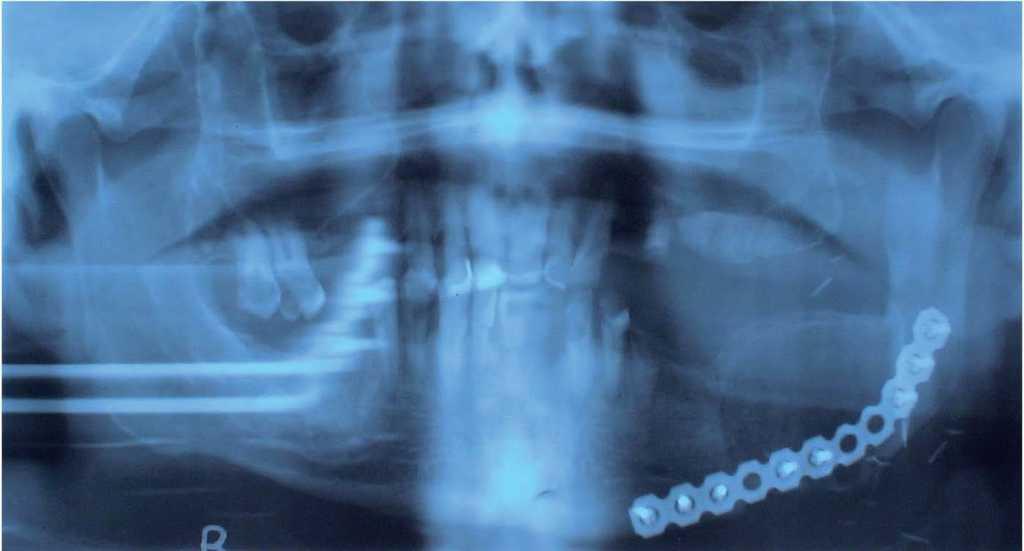

Fig. 4 – Nótese la osteosíntesis de la cresta ilíaca en los remanentes mandibulares.

Caso 3Varón de 43 años de edad. Presenta herida por arma de fuego como consecuencia de un intento suicida. Hay gran destrucción de partes blandas y óseas, que se reconstruyen de manera primaria mediante desbridamiento, sutura y osteosíntesis. Presenta una gran pérdida ósea del tercio medio de la mandíbula. En su conjunto, el paciente requiere una gran reconstrucción del macizo facial. La reconstrucción secundaria de las lesiones se inicia con una reconstrucción mandibular. Para cubrir simultáneamente ambos defectos (cutáneo y óseo), se decide realizar un colgajo de cresta ilíaca con pala cutánea, con inclusión de una pequeña porción de músculo oblicuo interno para el cierre intraoral. Como se precisa de una gran movilidad tridimensional del islote cutáneo, se realiza el trasplante con un colgajo microquirúrgico de cresta ilíaca con doble pedículo vascular.